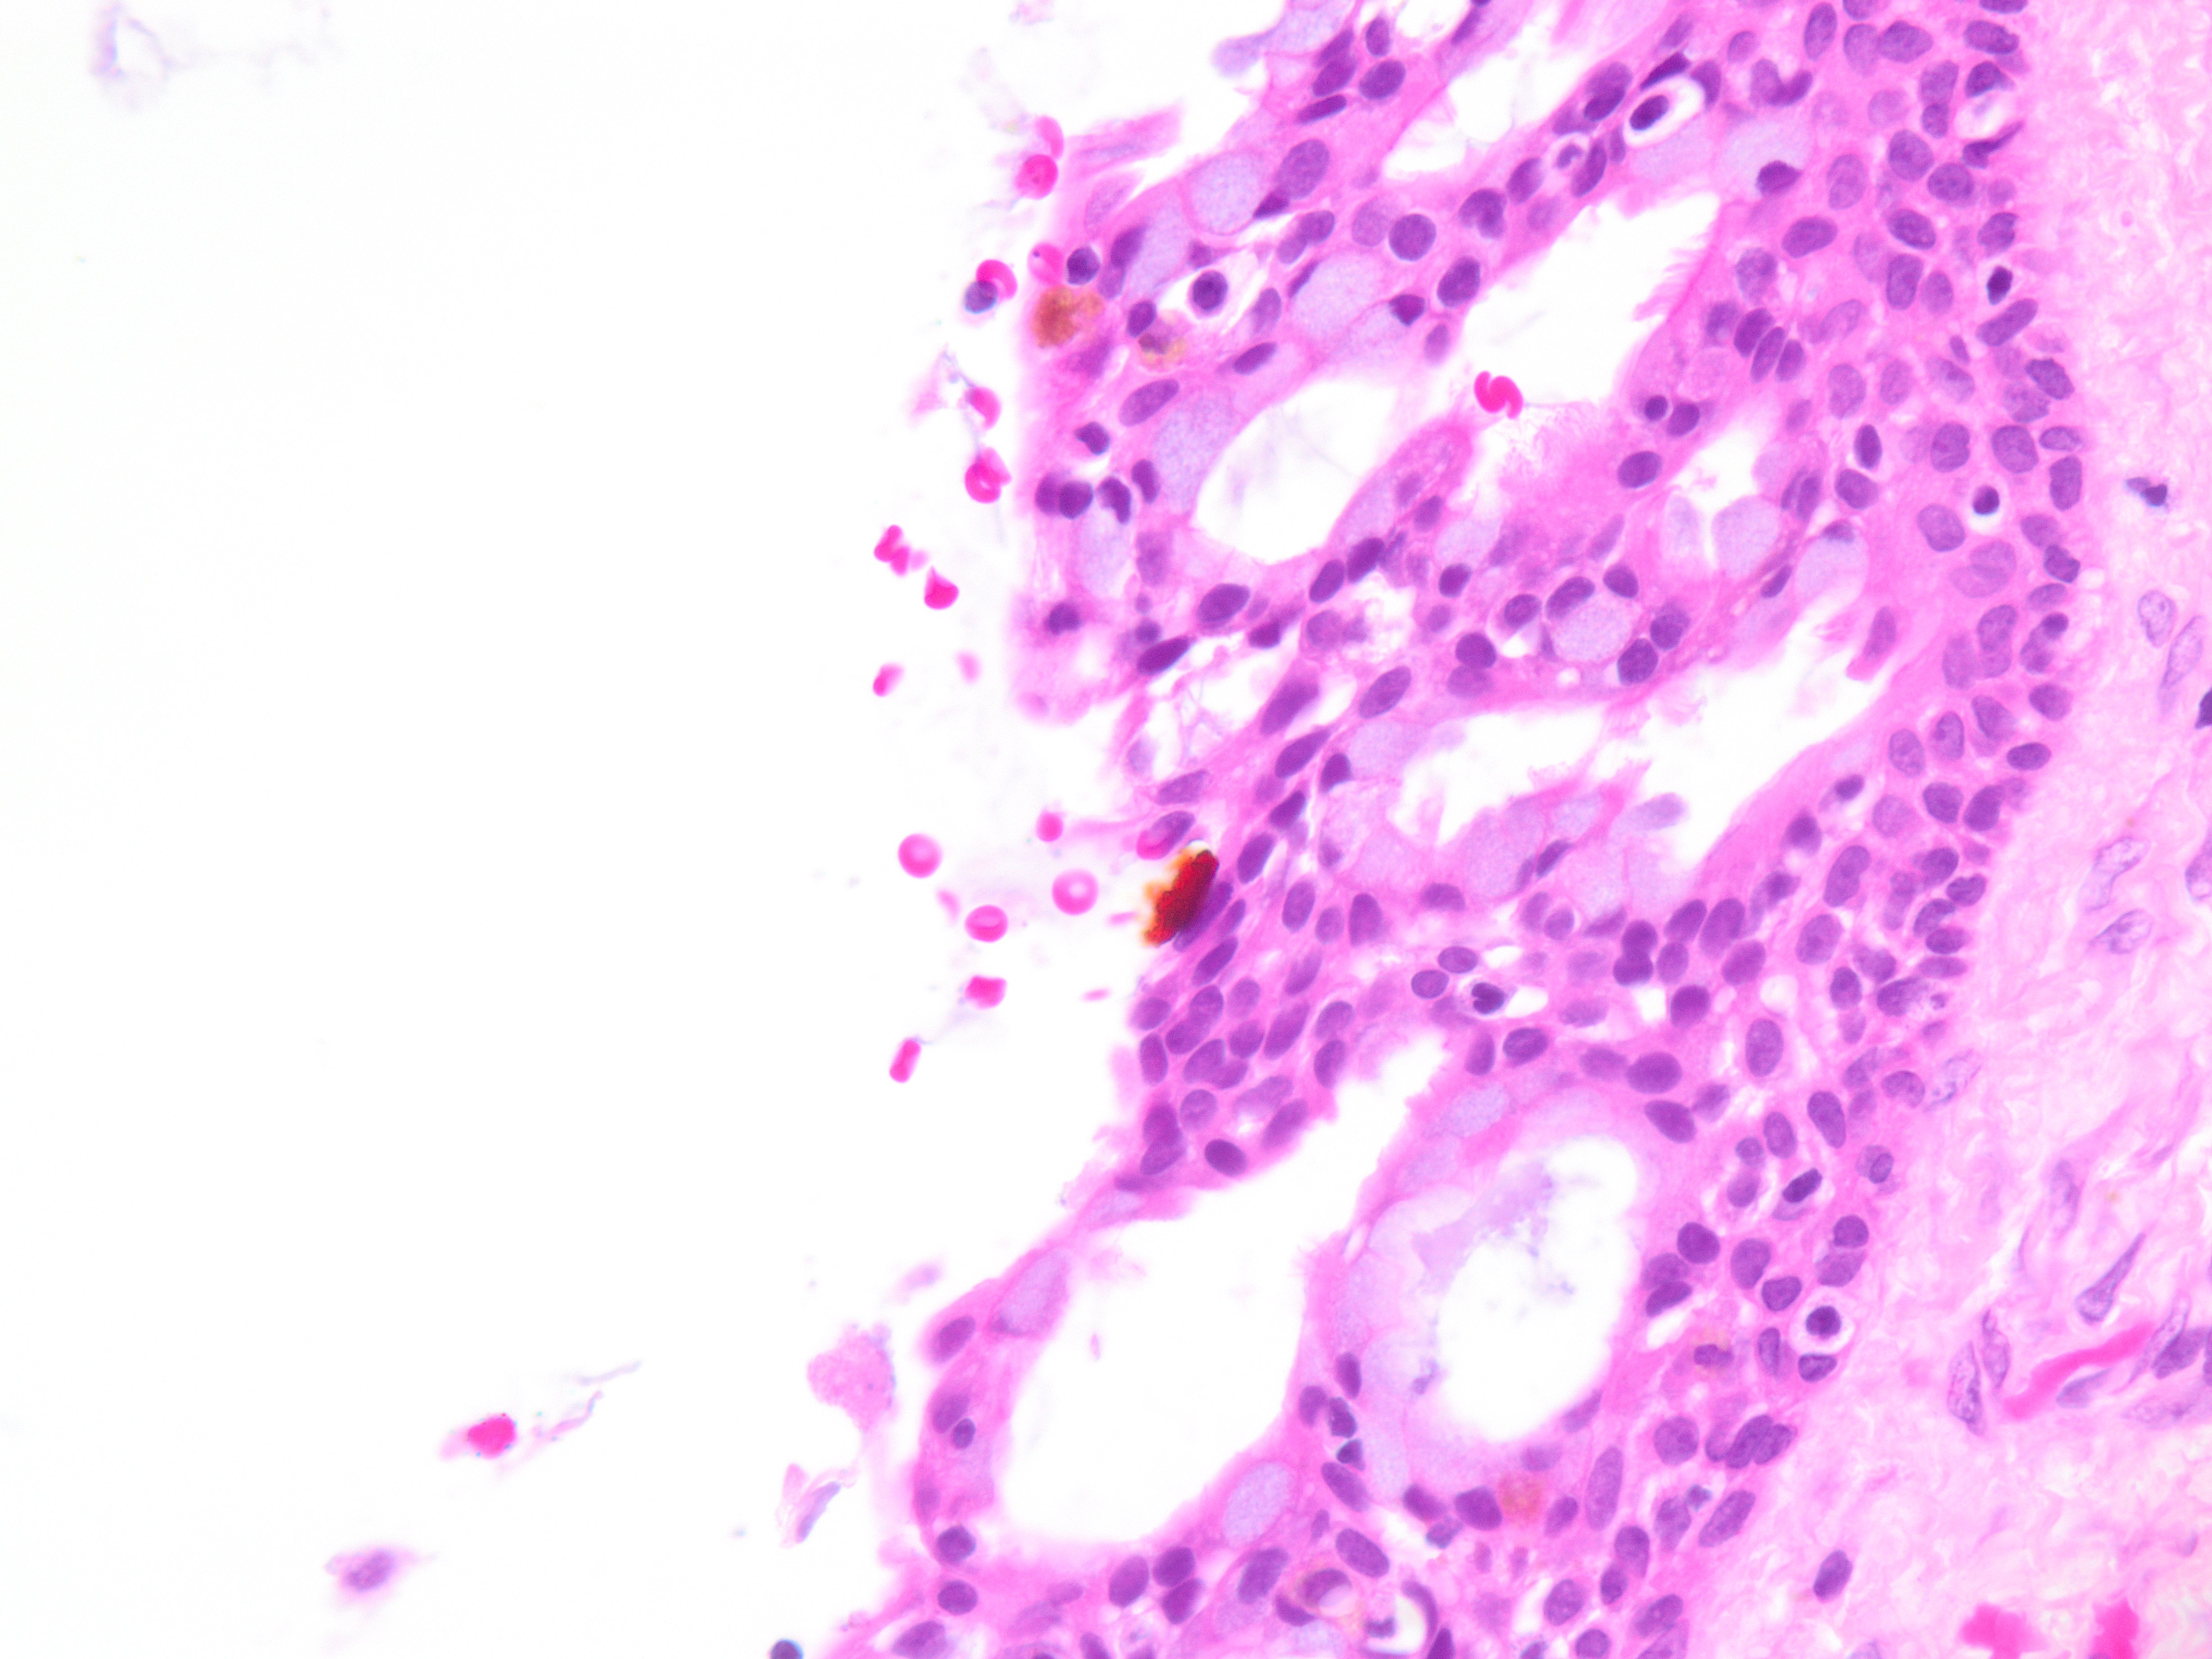

Brief explanation of the answer: Sections show cyst lining of variable thickness with mucous cells, ciliated cells, eosinophilic cuboidal cells, and clear cells. There are multiple compartments. Microcysts, papillary projections and epithelial spheres are present. These features are consistent with glandular odontogenic cyst. Resection is recommended due to high recurrence rate.

No basal cell palisading or parakeratin is noted, excluding odontogenic keratocyst. Periapical and radicular cysts tend to have a squamous lining with abundant inflammation. Mucoepidermoid carcimoma tends to be more proliferative with invasive features, and also shows intermediate and epidermoid cells.